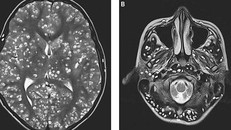

Kết quả chụp MRI cho thấy chàng trai có nhiều nang sán trong vỏ não (hình bên trái là các chấm trắng). Các tổn thương cũng được tìm thấy trong thân não và tiểu não của anh ta (nhìn bên phải).

(Ngày Nay) - Sau 2 tuần điều trị, bác sĩ vẫn không thể cứu được nam thanh niên do ấu trùng sán lợn đã xâm chiếm toàn bộ não.